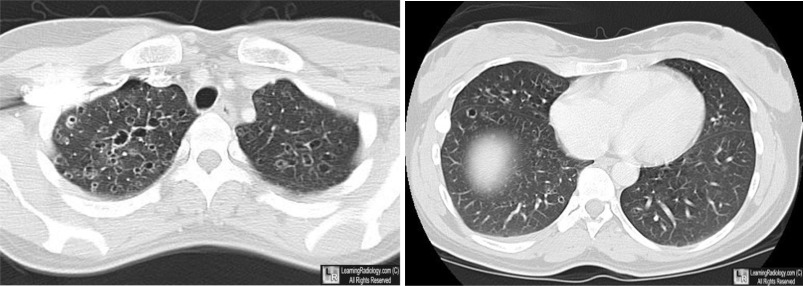

Eosinophilic Granuloma of the Lung. There are multiple, thin-walled cystic structures, greater in the

upper than the lower lobes, characteristic of this disease.